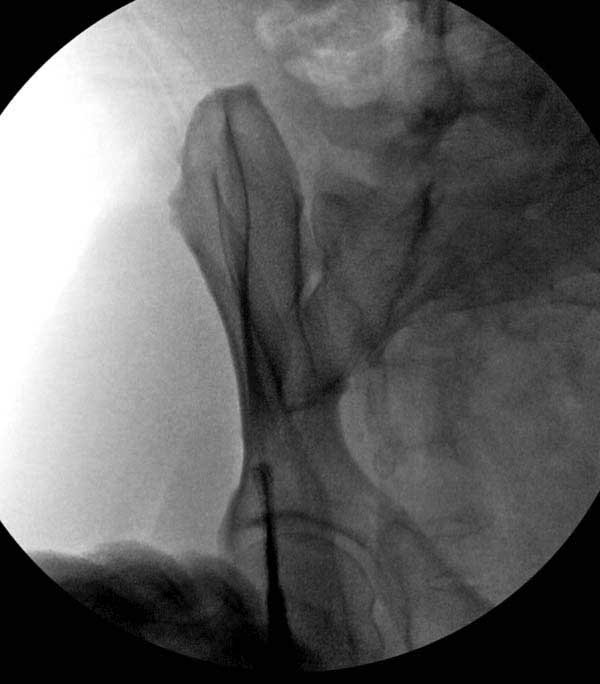

Здесь представлен случай 38 летнего больного (падение с высоты 9 метров) с нарушением тазового кольца. При поступлении для стабилизации передне-нижний аппарат наружной фиксации и на 6й день, вчера, операция из двух доступов.

Представлены снимки техники проведения стержней. Через место прикрепления прямой мышцы в Inferior Iliac Spine в направления вырезки создается жесткость. Weber clamp изнутри таза для репозиции, и фиксация после репозиции перелома крыла подвздошной кости. Наружный аппарат удален, нагрузка предполагается через два месяца.